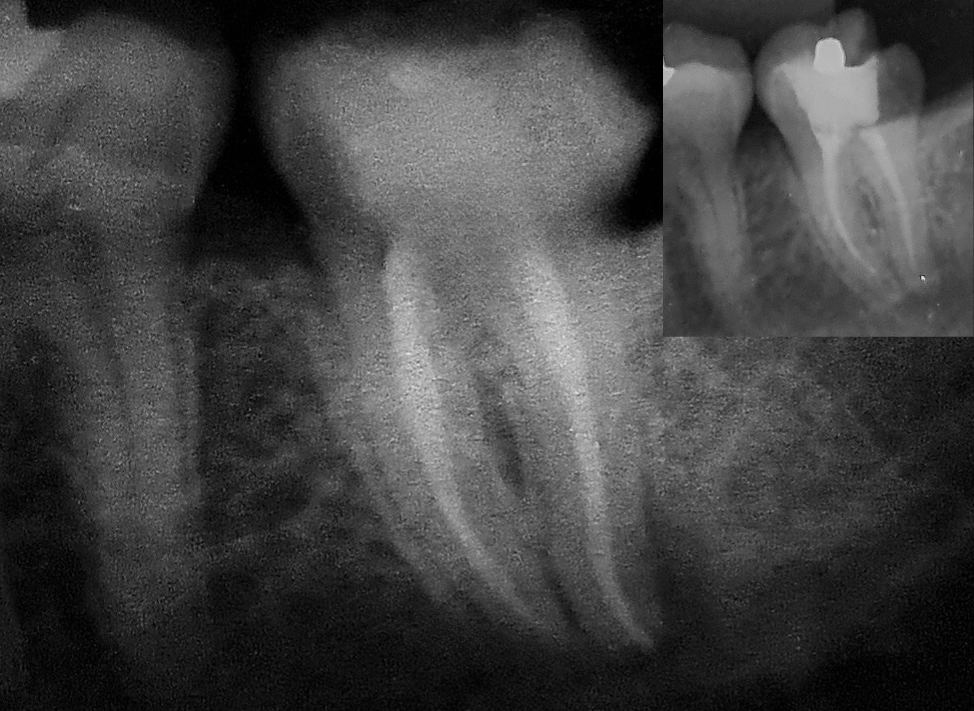

Molares com atresias e curvaturas, urgências endodônticas, dentes anteriores...

Remoção de elementos protéticos, retentores intra-radiculares (fibra de vidro e metálicos) e materiais obturadores.

Entusiasta da tecnologia – utiliza instrumentos mecanizados associados as técnicas atuais e clássicas respaldadas na Literatura endodôntica.

Sim, é necessário que a clínica esteja equipada com o aparelho de radiografia para possibilitar a documentação adequada do caso.